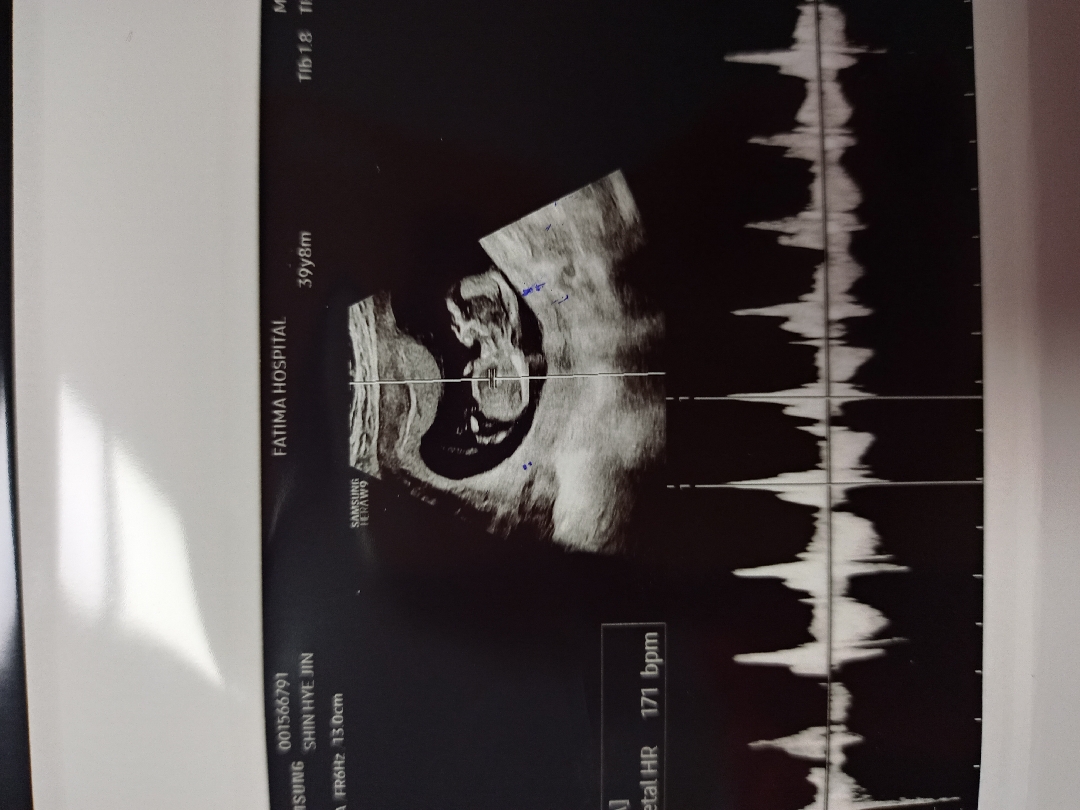

12주 각도법 어떤가요?

12주 초음파 보고 왔는데 어떤지 봐주세요~ 궁금해요^^